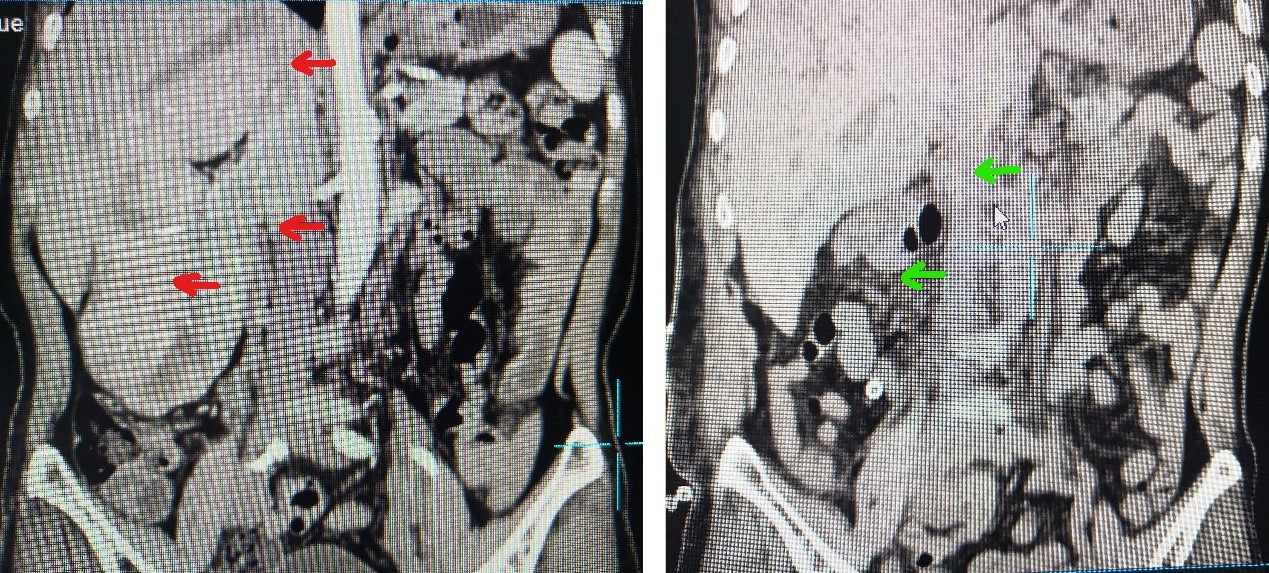

患者66岁女性诊断为右肾肿瘤伴长段下腔静脉瘤栓,下腔静脉内瘤栓长约7厘米,上端已经到达第一肝门水平,手术面临着出血风险大、涉及器官多、手术空间小等一系列难题,对翔安医院泌尿外科这么一个全新的科室而言仍然是不小的挑战。

(术前:红箭头指示肾肿瘤和瘤栓 术后:绿箭头指示右肾和瘤栓被完整切除)